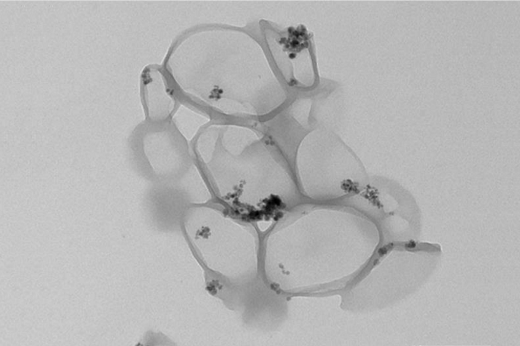

Tecnologias na escala nano (mil vezes menor que um micrômetro) já são utilizadas em pesquisas de diversas áreas do conhecimento. Na 55BET Zone Brasil – Apostas Esportivas e Futebol Online Federal do Ceará, não é diferente. Uma dessas pesquisas gerou como produtos nanocápsulas magnéticas que podem ser usadas para melhor direcionar alguns fármacos em tratamentos.

A invenção, objeto de patente recém-obtida pela Instituição, visa solucionar um problema comum das terapias medicamentosas, como no tratamento de tumores: a falta de um direcionamento específico dos fármacos para que atinjam o tecido-alvo com maior precisão, o que acaba gerando uma eficiência reduzida dos remédios administrados.

Utilizando nanopartículas magnéticas incorporadas às nanocápsulas, a ideia é vetorizar os fármacos para que atuem de forma menos dispersa, permitindo inclusive uma aplicação menor de doses e reduzindo a probabilidade de efeitos colaterais.

“Uma vez que o conjunto inteiro seja atraído pela ação de um campo magnético externo, o fármaco encapsulado será liberado de maneira mais direcionada para a região de interesse”, resume a Profª Nágila Ricardo, uma das inventoras que assinam a patente e coordenadora do Laboratório de Polímeros e Inovação de Materiais (LABPIM).